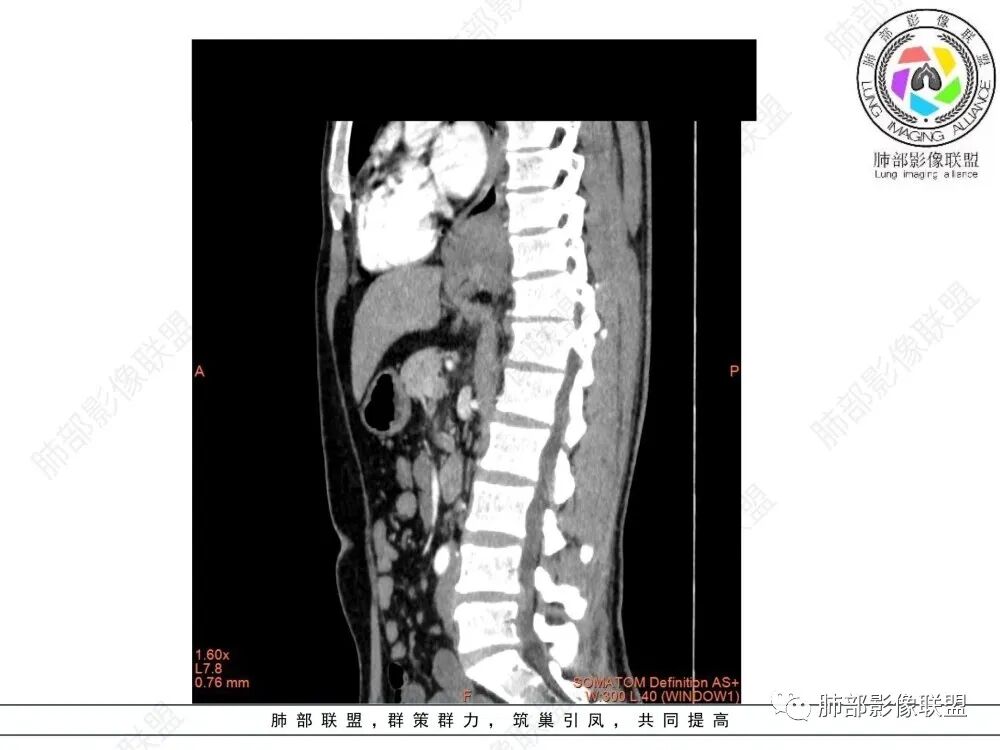

影像学特点:类纵隔区病变,沿食管生长,形态不规则,但边界清楚,内部信号/密度均匀,强化程度比较弱。

影像诊断思路:起源食管肿瘤(非黏膜起源,肌层起源),良性或低度恶性肿瘤可能性大,一般以神经鞘瘤、胃肠间质瘤及平滑肌瘤为主。食管神经鞘瘤强化明显均匀、以食管上段多见,周围常见炎性增大淋巴结,不太符合;胃肠间质瘤小的比较均匀,大的不均匀,但强化程度较高;影像上看这例病例比较符合平滑肌瘤。

食管平滑肌瘤是最常见的食管良性肿瘤,多见于男性,男女之比为2.6:1,高发年龄 30~60岁之间与食管癌相比,食管平滑肌瘤 的一个主要特点是病史相对较长,病情进展缓慢。病史最长者达10年余,平均 15.7个月,尽管病史较长,但大多数患者仍能进普食。食管平滑肌瘤的诊断一般比较容易,结合患者临床症状、食管造影及食管镜所见,一般均能得出正确诊断。食管造影主要为充盈缺损,病变与食管壁成锐角,粘膜线连续无破坏,管腔收缩扩张比较自如。钡餐造影敏感性高,但对食管壁间及食管周围情况难以判断。CT具有极高的密度分辨率,并且可以获得高质量的多平面重组图像,有利于食管壁间及食管周围情况的判断,表现为食管下段环绕管壁生长,偏心性或薄厚不均软组织密度肿块,密度均匀,内缘分叶状,管腔与正常食管壁构成不规则多角形扩张,增强动脉期无强化,多角度重建其病灶长轴与食管长轴不一致。由于食管壁在收缩状态下厚度约为5.6mm,扩张状态厚度不超过3mm,CT扫描时保持食管处于扩张状态可提高小病灶检出率。MR表现为T1加权等信号,T2加权稍高信号,可见高信号粘膜层,增强扫描轻度渐进性强化,密度均匀,无出血坏死。对于粘膜及周围脂肪间隙的判断具有明显优势。